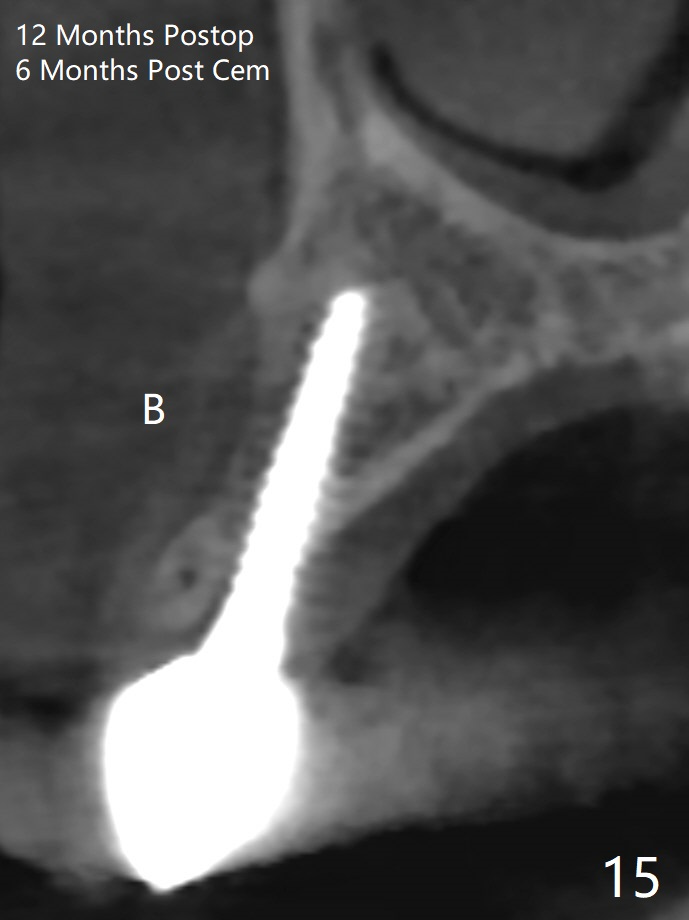

Osteotomy starts with guide and 2.2 mm drill for initial 3.5 mm palatal. A semilunar incision is made buccal to remove the impacted canine (#6 by sectioning). With direct vision buccal and palatal, the final osteotomy is finished free hand with 1.2 and 1.5 mm drills. Initially buccal perforation occurs, the osteotomy route is corrected later (Fig.1). When a 2.5x15 mm 1-piece implant is being placed, it perforates into the buccal concavity again. After redirection, the trajectory seems to be acceptable (Fig.2: CT coronal section). Three coronal implant threads are exposed partially palatal (Fig.3: CT 3-D palatal view). The implant is then turned 2-3 times with insertion torque reaching 40 Ncm. The incision is closed with suture following Osteogen plug placed in the most coronal portion of the socket (Fig.4 P) and allograft (*) in the remaining socket around the apical portion of the implant as well as palatal. The incision does not heal 1 month postop (Fig.5). PRF membrane will be placed next visit. Next visit the wound in fact is healing (Fig.6). PRF is unnecessary. The patient will return for impression 3 months postop. To be cosmetically pleasing, prepare local anesthetic and Laser for gingivectomy (Fig.7 red curved line). There is no bone loss around the implant 3.5 months postop (Fig.8). With topical, minor gingivectomy with laser creates papillae mesial and distal to the implant (Fig.9, 10 (incisal view)). After reline, there is appearance of a canine (Fig.11). The patient returns for impression 5 months postop; there is bone around the apex of the implant (Fig.12 *). The hard and soft tissues remain healthy when final restoration is delivered (Fig.13,14). The buccal plate reforms and #6 socket heals 12 months postop (6 months post cementation, Fig.15). The gingiva remains healthy at #4-6 nearly 2 years post cementation (Fig.16).